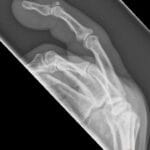

- Radiology Cases: Images with a to-the-point discussion highlighting the specific diagnostic criteria.

- Radiology Case of the Day Collection: Aunt-Minnie Board Cases for Rapid Review.

- Radiology Spotters: 700+ spot / “Aunt-Minnie” cases divided into sets of 10 each!